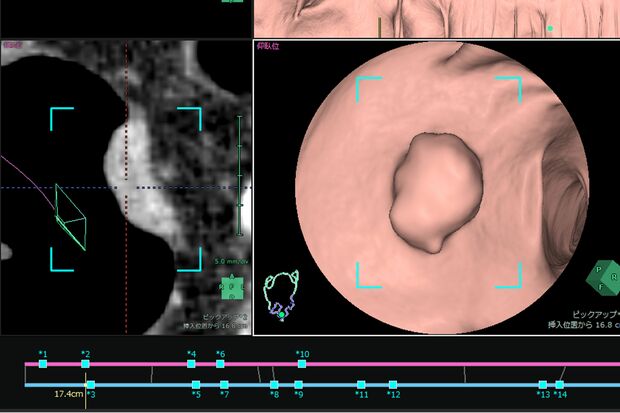

CTコロノグラフィーによる検査は、肛門にチューブを挿入して炭酸ガスを注入し、大腸を膨らませた状態でCT撮影を行い、内視鏡で見るような3D画像を再構成して観察・診断する方法。病変の位置が正確にわかり、大腸内視鏡の死角に存在する病変を発見することも。画像提供/富士フイルム株式会社

[写真 2/7枚目] CTコロノグラフィーによる検査は、肛門にチューブを挿入して炭酸ガスを注入し、大腸を膨らませた状態でCT撮影を行い、内視鏡で見るような3D画像を再構成して観察・診断する方法。病変の位置が正確にわかり、大腸内視鏡の死角に存在する病変を発見することも。画像提供/富士フイルム株式会社